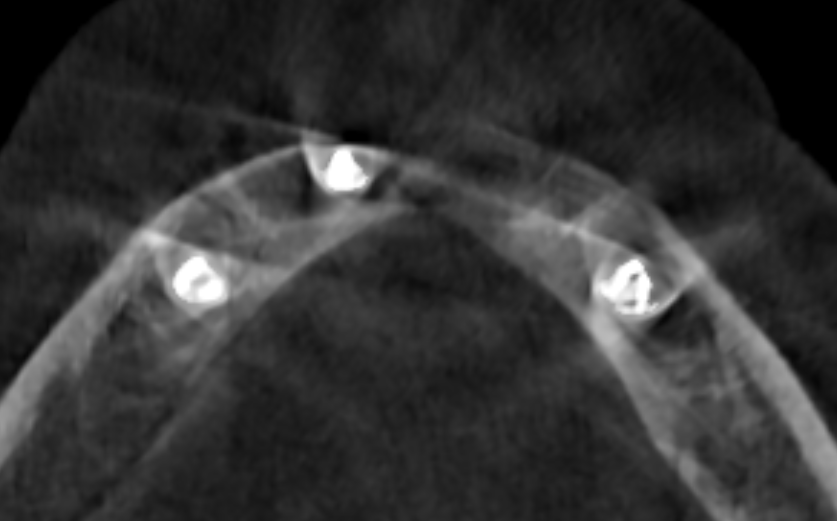

Just like in a regular CT scan, the CBCT image is made up of millions of tiny 3D boxes called voxels. Each voxel gets a Grayscale Value (GV), also known as a Voxel Value, that represents the amount of X-ray beam that was blocked by the tissue inside that box.

- High GV (Bright White): This means the tissue blocked a lot of X-rays (like tooth enamel or dense bone).

- Low GV (Dark Black): This means the tissue blocked very few X-rays (like air).

- In-Between GV (Shades of Gray): This is for everything else, like muscles and soft tissue.

Scan 1: Patient with Denture

- Content: Patient’s skull (very dense bone) + Denture (acrylic/markers).

- Scaling: The CBCT sees a huge range of densities. The skull is the densest thing, so the machine sets its GV very high. The denture material is much less dense than the bone, so it gets a lower, less dramatic GV and can be hard to see clearly against the soft tissue.

- Result: You clearly see the skull and the denture is faint or hard to distinguish.

Scan 2: Denture Only

- Content: Just the Denture (acrylic/markers) + Air + Foam block (very low density).

- Scaling: The skull is gone! The denture material is now the densest thing in the picture. Because the machine scales the GVs to the maximum density in the current field of view, the denture material is now assigned a very high GV.

- Result: The denture appears bright white and clear in the image, as if it’s bone!